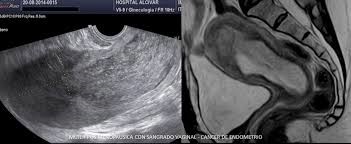

El cáncer de endometrio es una patología oncológica que tiene como características que principalmente afecta a mujeres en la etapa post menopaúsica y se presenta frecuentemente con la presencia de un sangrado vaginal y luego de estudios de imágenes como la ecografía se observa un endometrio engrosado ( > 4/5 mm). Ante la presencia de este cuadro se realiza una HISTEROSCOPIA que es un estudio endoscópico de la cavidad endometrial que nos permitirá realizar biopsias dirigidas .Ante la presencia de un diagnostico oncológico , se realiza un tratamiento acorde al grupo HISTOLOGICO del tumor . Por lo que es fundamental que te atiendas con un GINECOLOGO ONCOLOGO que va a poder elegir el tratamiento correcto para vos , que frecuentemente es la realización de una ANEXOHISTERECTOMIA con manguito vaginal mas linfadenectomía pelviana y lumboaortica (extirpación de útero, ovarios y ganglios) en algunos casos determinados todo dependiendo del grado tumor y la familia histológico como me referi previamente.